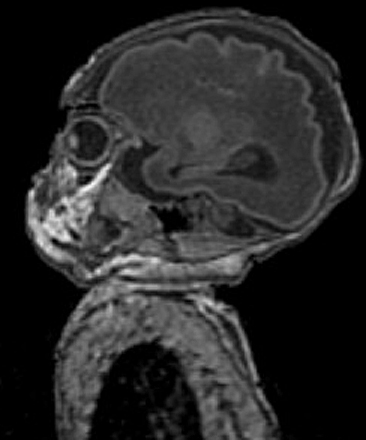

UCSF Leads the Way in Neonatal Neuroimaging with MRI

Newborn babies, whether born prematurely or at term, have a very different brain than a mature child. The brain is very small, the connections have not been fully established or matured, and the axons, the long processes that connect the nerve cells and allow intercommunication among them, have not yet been covered with myelin, a substance that increases the speed of transmission of communication. In addition, the immature brain is at significant risk for injury, in part because other body systems, including the heart, lungs, blood vessels, and immune system, are still immature. The immaturity of the nervous system makes neurological examination very challenging, even for experts. Therefore, brain imaging is a crucial test to evaluate newborns who are suspected of having suffered any sort of injury.

With the help of child neurologists, neonatologists, and imaging scientists, neuroradiologists at UCSF have pioneered the use of Magnetic Resonance Imaging (MRI) to look for any evidence of injury or abnormal development in the brains of newborns. This sort of medical imaging evaluation is not easy. It requires specialized nurses and doctors to transport the baby safely to the MRI scanner and back to the Intensive Care Nursery. It also requires specially designed protocols that allow assessment of brain anatomy, identification and specification of any areas of injury (including blood), assessment of blood flow, assessment of the microstructure of the brain, and assessment of brain chemistry. This information is used to diagnose the injury, but also to help in finding the cause of the injury and to provide rapid feedback about whether treatments are working. These MRI studies have made a very significant contribution to the decreased frequency of neonatal brain injury and the improved outcomes of injured neonates over the past 20 years.